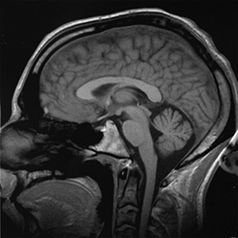

في الحيوانات, المخ أو الدماغ (باليونانية: Encephalon وتعني "في الرأس"), هو مركز تحكم الجهاز العصبي المركزي, المسئول عن التصرف. والمخ يقع في الرأس, محمياً بالجمجمة وقريباً من الجهاز الحسي الرئيسي vision, السمع, equilibrioception (اتزان), حاسة التذوق, والشم. وبينما كل الفقاريات لديها مخ, إلا أن معظم اللا فقاريات لديها إما مخ مركزي أو مجموعات من ganglia الفردية. الحيوانات البدائية مثل الاسفنج ليس لديها مخ على الاطلاق. والأمخاخ قد تكون معقدة للغاية. فعلى سبيل المثال, المخ البشري يحتوي على أكثر من 100 بليون neurons, each linked to as many as 10,000 other neurons.

يشكل يشكل 85% من إجمالي وزن الدماغ. ويقسم شق كبير يسمى الشق الطولي المخ إلى نصفين يسميان نصف الكرة المخية الأيمن ونصف الكرة المخية الأيسر. ويتصل النصفان بحزم من الألياف العصبية ، يسمى أكبرها الجسم الثفني. وينقسم كل نصف بدوره إلى أربعة فصوص، يسمى كل منها باسم عظمة الجمجمة التي تقع فوقه. والفصوص هي:

وتكوِّن طبقة رقيقة من الخلايا العصبية تسمى [[القشرة المخية أو القشرة الجزء الخارجي من المخ. ويتكون معظم المخ تحت القشرة من ألياف من الخلايا العصبية. وتربط بعض هذه الألياف أجزاء القشرة بعضها ببعض، بينما تربط ألياف أخرى القشرة بالمخيخ وجذع الدماغ والحبل الشوكي.

والقشرة المخية مطوية في شكل سطح كثير النتوءات والأخاديد. ويزيد هذا الطي المساحة السطحية للقشرة، وعدد الخلايا العصبية التي تحتويها في الفراغ المحصور بالجمجمة. وتستقبل بعض مناطق القشرة المخية، المسماة القشرة الحسية الرسائل القادمة من الأعضاء الحسية، بالإضافة إلى رسائل اللمس ودرجة الحرارة من أجزاء الجسم المختلفة. وترسل مناطق في الفص الجبهي تسمى القشرة الحركية، الدفعات العصبية التي تتحكم في الحركات الإرادية لكل العضلات الهيكلية. وأكبر أجزاء القشرة حجمًا هو قشرة الترابط، حيث يحتوي كل فص على قشرة ترابط يحلل المعلومات ويعالجها ويخزنها. وقشرات الترابط هي التي تمكِّن الشخص من أداء النشاطات التي تتطلب قدرات عالية مثل التفكير والتحدث والتذكر.